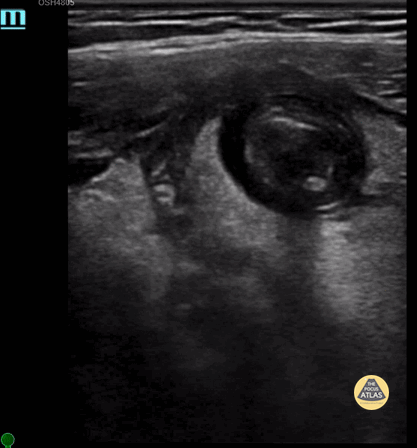

Transverse view of the appendix showing the appendix with intraluminal appendicolith. Contributor: Maher M. Abulfaraj, MD, @mahermabulfaraj